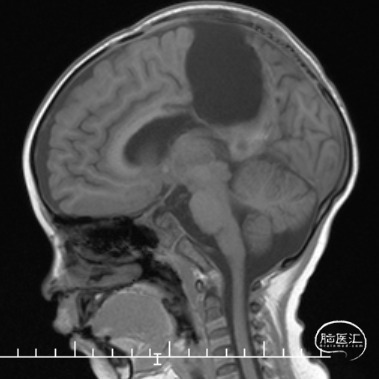

双侧额顶叶中线旁脑实质内团片状异常信号影,呈明显花环状强化,累积脑膜及胼胝体压部,性质待定,恶性胶质瘤?

本例患儿肿瘤位于双侧额顶叶,大脑镰旁,增强扫描呈明显环形强化,提示肿瘤血运丰富。患儿年龄小,体重低,相对血容量少,如何控制术中出血是手术成功的关键。而术后肢体瘫痪或瘫痪加重是手术的主要并发症,中央沟静脉损伤、胼周动脉损伤、中央沟局部皮层损伤、癫痫、血肿以及脑水肿加重是其常见原因。术前脑血管造影有助于判断肿瘤与周围血管、组织的位置关系,明确上失状窦有无闭塞,对手术的切口设计有重要的参考价值及避免术中损伤不易发现的血管及组织。

本例患者术前脑血管造影提示瘤体主要由双侧大脑前动脉终末分支供血,造影静脉期瘤体显影明显,因此我们选择先采用神经介入技术超选部分主要供瘤动脉予弹簧圈栓塞,减少瘤体的供血。之后再行开颅探查双侧额顶叶占位性病变切除术。

非典型畸胎瘤样/横纹肌样瘤( AT /RT) 是发生在儿童中枢神经系统的少见的具有极大侵袭性的恶性肿瘤,在儿童中枢神经系统肿瘤中发病率极低。CT平扫多表现为混杂密度,也可等或稍高密度,呈不均匀或均匀强化,瘤内常可见囊性变及瘤周低密度水肿带。MRI扫描T1加权像为低信号,T2加权像为等信号或高信号,肿瘤实质与灰质信号相似或稍高,增强扫描可见中等至明显 增强,等信号时可能与肿瘤细胞密集,细胞核比例大而含水量相对较少有关。AT /RT是原发于中枢神经系统、好发于儿童、极其少见、侵袭性极高的胚胎性肿瘤,临床表 现及影像学无特异性,确诊有赖于组织病理。最大限度的安全切除,并辅以放化疗,可改善患者预后,但总体预后仍然很差。